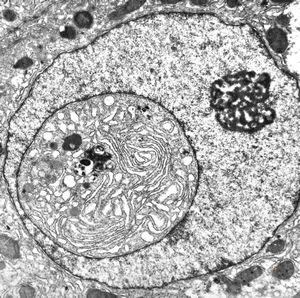

F,61y. | intranuclear cytoplasmic inclusion - giant cell hepatitis